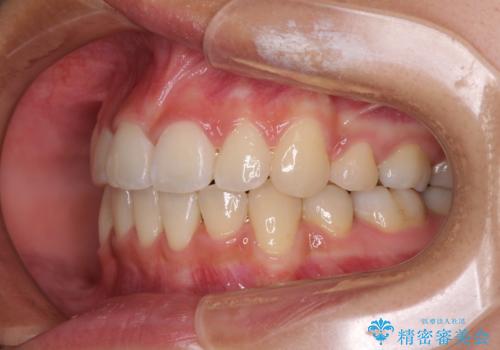

半年ほどで前歯のデコボコは改善され、汚れの溜まりやすさは解消されました。

抜歯スペースを閉じるために期間がかかりましたが、当初予定通り2年強で終えることができました。